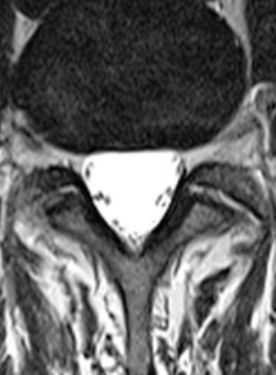

МРТ позвоночника. Аксиальная Т2-взвешенная МРТ. Нормальный срез через дугоотростчатые суставы.

После того, как появилась ясность в способе получения МРТ изображений позвоночника, надо понять какие анатомические структуры видны. Счет позвонков ведется разными способами - сверху от зубовидного отростка С2 (осевой позвонок), от бифуркации трахеи Т5 ( пятый грудной, с погрешностью на 1 позвонок) или снизу от L5 (последний поясничный), также не исключена погрешность на 1 позвонок в связи люмбализацией или сакрализацией. Анатомия позвоночника в МРТ изображении представлена в нашей другой статье. На серии сагиттальных Т2-взвешенных МРТ позвоночника видны асе основные структуры, причем удается проследить ход корешков конского хвоста. В поясничном отделе он идет под углом вниз и выходит через межпозвоночное отверстие нижележащего позвонка. Аксиальные (поперечные) МРТ срезы всегда делаются вдоль межпозвоночного диска, то есть с учетом нормальных или патологических изгибов позвоночника. Они наиболее удобны для оценки состояния дугоотростчатых суставов. При МРТ позвоночника в поперечной плоскости МРТ срезы часто делают на разных уровнях для лучшей визуализации состояния корешков по их ходу - в дуральном мешке, затем боковом кармане дурального мешка, далее в межпозвоночном отверстии и, наконец, после выхода из него. Таким образом, в поперечном МРТ срезе позвоночника через межпозвоночное отверстие на поясничном уровне можно видеть отрезки сразу двух корешков - вышележащего на выходе из отверстия, и нижележащего в боковом кармане.